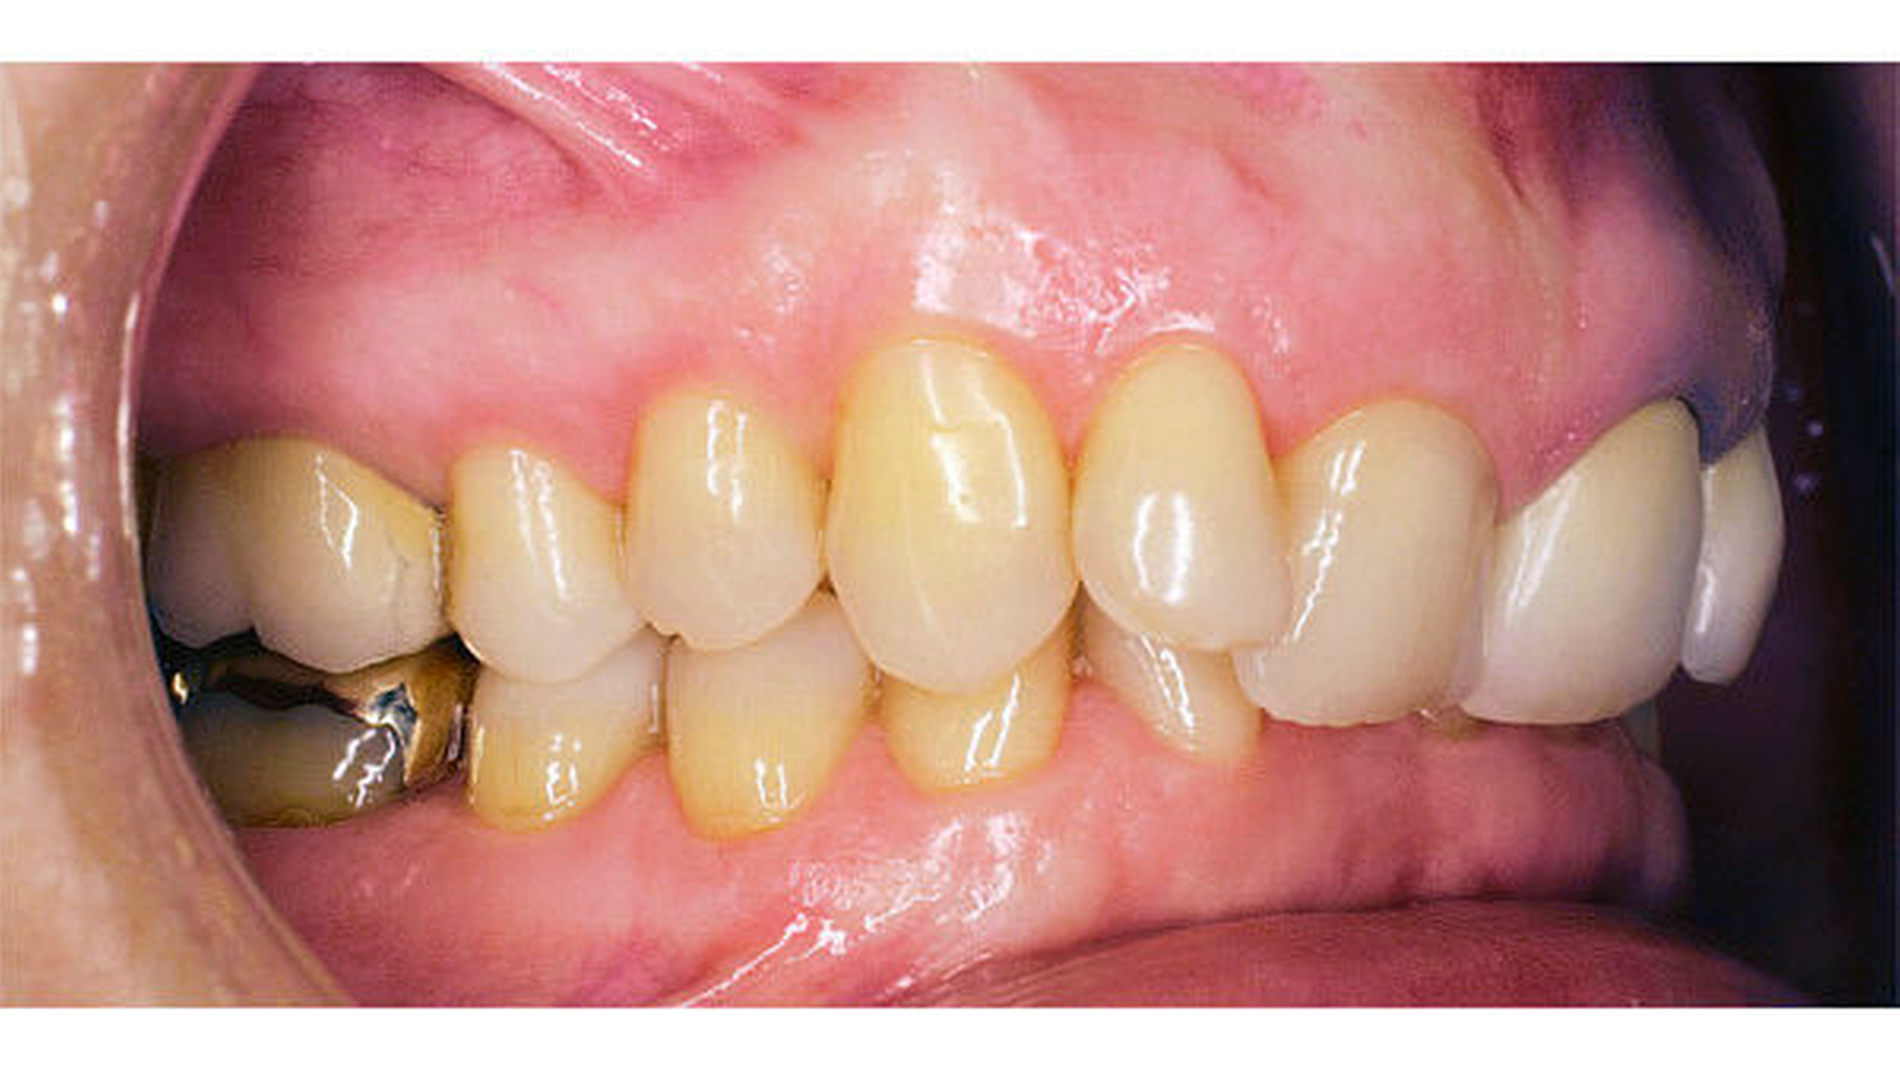

Auch wenn manche Patienten und auch einige Kollegen die Stellung der Zähne im Zahnbogen als „stabil“ bezeichnen oder wahrnehmen, zeigen Langzeitbeobachtungen in der Kieferorthopädie, dass Zähne langfristig wandern. Es müssen nicht immer Rezidive nach einer kieferorthopädischen Behandlung sein [Rudzki und Kirschneck, 2017], die die Patienten beunruhigen, es können auch ganz andere, neue Zahnwanderungen stattfinden (Abbildungen 3a bis 3c)

Heute sehen wir in den kieferorthopädischen Praxen immer mehr Patienten, die deutlich älter als 50, 60 oder gar 70 Jahre alt sind, deren Zähne so weit aus dem Zahnbogen herausgewandert sind, dass wir sie wieder „einfangen“ müssen (Abbildung 3a, Abbildungen 6a bis 6d).

Mit der Mesialdrift wird immer wieder auch die interdentale Abrasion genannt. Dies ist von prähistorischen Gebissen oder von den Zähnen bestimmter Naturvölker bekannt [Alt and Türp, 1996; Alt et al., 1998]. In ihrem Ausmaß entspricht die interdentale Abrasion aber heute oft nicht der Zahnwanderung nach mesial. Möglicherweise wären die Engstände noch deutlicher sichtbar, wenn sie gar nicht stattfinden würde. Jedenfalls wird beobachtet, dass bei einer stark eng stehenden Unterkieferfrontzahngruppe durchaus eine Mesialbewegung der Seitenbezahnung stattgefunden haben kann. Wenn die Okklusionsbeziehungen im Seitenzahnbereich gut sind, kann daraus gefolgert werden, dass auch die Seitenzähne im Oberkiefer im gleichen Takt nach mesial gewandert sind (Abbildungen 6c und 6d). Ein entsprechender Engstand in der Frontzahngruppe im Oberkiefer wird aber nicht in jedem Fall vorgefunden. In solchen Fällen ist davon auszugehen, dass im Bereich der Frontzähne des Oberkiefers in verschiedener Ausprägung ebenfalls eine gewisse interdentale Abrasion stattfindet, aber nicht im Unterkiefer: Dort haben sich die schmalen Zahnkronen durch Rotation einer interdentalen Abrasion entzogen (Abbildung 6b). Dieses Szenario wird oft beobachtet, aber es besteht durchaus noch Forschungsbedarf, um die Zusammenhänge zu verstehen.